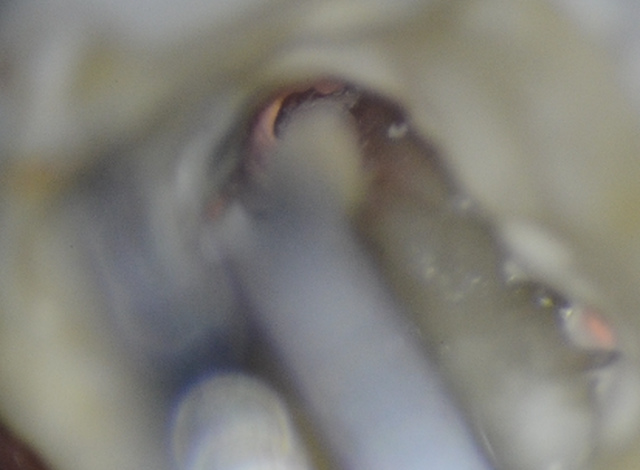

- diagnozowanie i zamykanie perforacji dna komory lub korzenia (ryc. 2),

Ryc. 2a do 2c. Perforacja w obrębie ujścia kanału podniebiennego powstała podczas preparowania łoża pod wkład koronowo-korzeniowy: (A) umieszczenie grubego sączka w obrębie kanału perforacyjnego, (B) wierzchołek sączka przebarwiony krwią, (C) w ujściu kanału widoczna gutaperka (strzałka zielona), ślad krwi (strzałka żółta) i perforacja (strzałka czerwona).